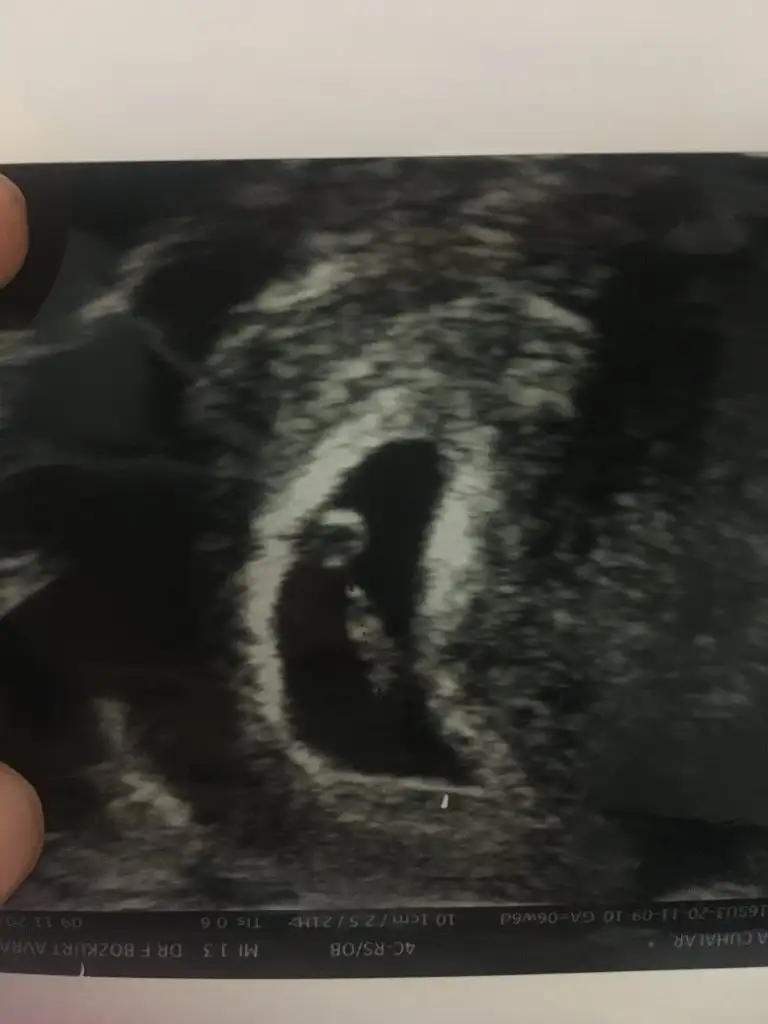

dr soylemeden siz gorun genital nub teorisi ( bebegin cinsiyeti)

Merhabalar biraz büyüdük tekrar geldik 12+2 karından bakıldı bi tahmininiz varmı 😊